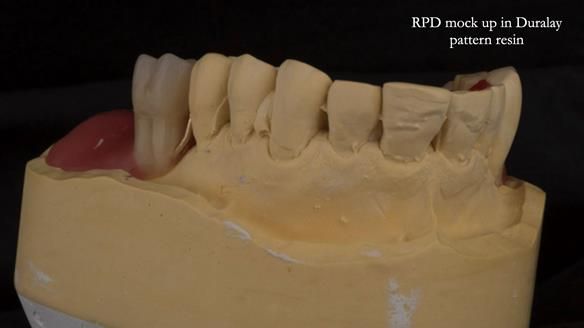

An honest note on the impressions

It’s important to say that I struggled considerably to obtain accurate impressions of Ken’s lower anterior teeth. This was a difficult situation and not one that went smoothly.

At one stage, a tray became locked in position and had to be sectioned and removed carefully. This is not something I like but it does happen, particularly in cases with long, thin teeth and compromised anatomy.